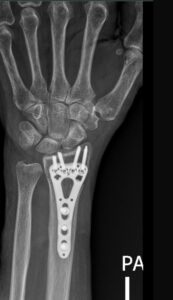

For complex or unstable fractures, wrist surgery may be necessary. Dr. Ehab Aldlyami offers:

- Open Reduction and Internal Fixation (ORIF): Using a titanium plate and screws to realign the bone